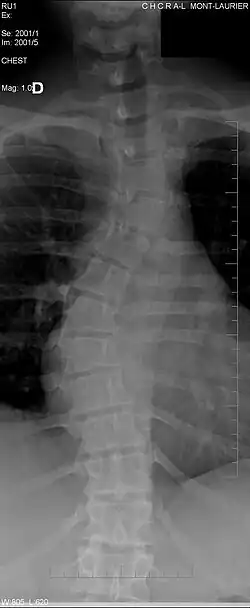

La scoliose

Même si elle ne cause pas forcément des douleurs chez les patients, elle reste responsable de certaines douleurs chroniques. Elle entraîne des troubles morphologiques de la colonne vertébrale et des disques intervertébraux. Par exemple, les patients atteints de scoliose ont souvent des dépôts de calcium (calcification ectopique) dans les cartilages périphériques et parfois dans le disque lui-même[11]. En plus de la scoliose, qui courbe latéralement la colonne vertébrale en " S ", les vertèbres peuvent également présenter des anomalies entraînant une cyphose (bossu) lié avec l'âge, ou une lordose (creux) qui est souvent liée à la grossesse ou l'obésité.

Un trouble de l'espace entre deux vertèbres est généralement détecté par rayons X et caractérise un espace anormal entre deux vertèbres. Chez les patients sains cet espace correspond à l'épaisseur d'un disque intervertébral sain, mais il peut devenir plus élevé dans des cas pathologiques (cas de spondylodiscite avec infection du disque intervertébral)[12].